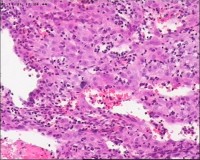

性别

女

年龄

20岁

停经3月,阴道不规则流血7天。

宫刮物

灰白灰红碎组织一堆,大小为7*6*1cm,部分组织呈水泡状

水肿的绒毛和蜕膜,没看到增生的滋养细胞。必要时可做IHC除外部分葡萄胎,并结合临床HCG。

考虑葡萄胎